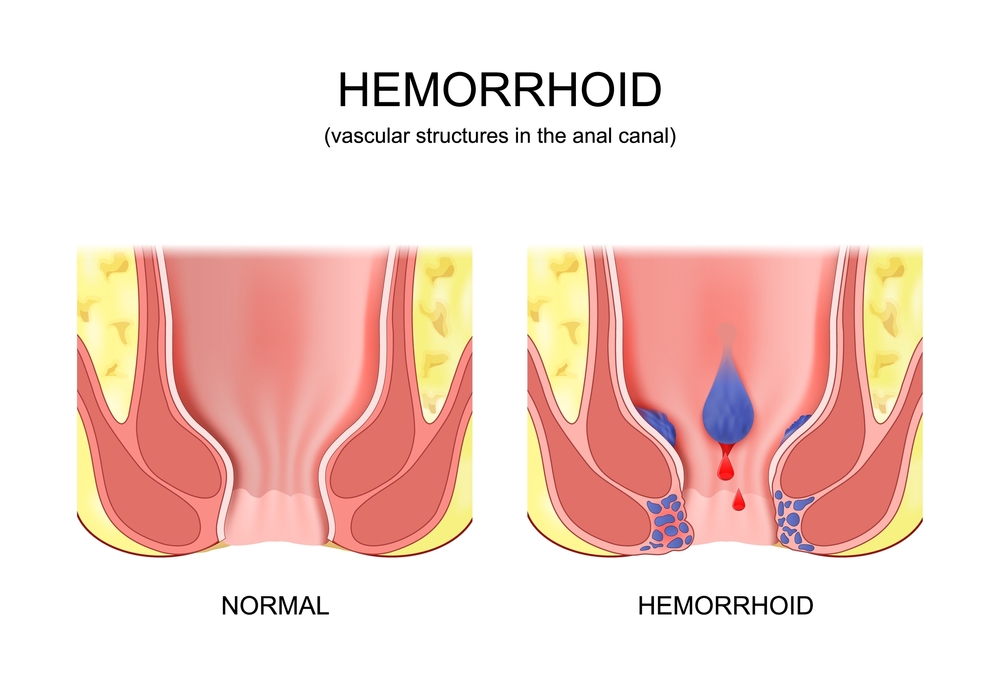

هموروئید؛ یکی از پیامدهای نادیده گرفتن یبوست

یبوست مزمن، اگر به موقع درمان نشود، تنها یک اختلال گوارشی ساده باقی نمیماند؛ بلکه میتواند به مرور زمان زمینهساز بروز بیماریهای دردناکتری مثل بواسیر (Hemorrhoid) یا همان هموروئید شود. بواسیر یکی از رایجترین عوارض ناشی از اختلال در دفع است که میلیونها نفر را در سراسر جهان درگیر میکند.

بواسیر چیست؟

بواسیر، در واقع التهاب و تورم وریدهای ناحیه مقعد و انتهای راستروده است که میتواند داخلی (درون مقعد) یا خارجی (در اطراف دهانه مقعد) باشد. این رگها به طور طبیعی در بدن وجود دارند، اما هنگامی که فشار داخل شکم یا راستروده افزایش مییابد، دیواره آنها گشاد و ضعیف شده و به صورت تودههایی متورم ظاهر میشوند.

علائم رایج بواسیر

علائم بواسیر ممکن است بسته به شدت و نوع آن (داخلی یا خارجی) متفاوت باشد، اما شایعترین نشانهها عبارتند از:

خونریزی بدون درد هنگام دفع مدفوع (معمولاً روی دستمال توالت یا در کاسه توالت دیده میشود)

احساس توده یا بیرونزدگی در ناحیه مقعد

درد، سوزش یا خارش در اطراف مقعد

تورم، التهاب یا احساس سنگینی در ناحیه تحتانی رکتوم

در موارد پیشرفته، ترشح مخاط یا بیاختیاری جزئی در دفع

اگر بواسیر درمان نشود چه میشود؟

بیتوجهی به بواسیر یا درمانهای ناقص، میتواند باعث تشدید وضعیت و بروز عوارضی مانند لخته شدن خون در توده هموروئیدی (ترومبوزه)، عفونت موضعی، کمخونی ناشی از خونریزی مزمن و حتی نیاز به جراحیهای سنگین شود. بسیاری از بیماران به دلیل خجالت یا تصور اشتباه از بیخطر بودن این بیماری، آن را نادیده میگیرند؛ در حالیکه درمان بهموقع میتواند از پیشرفت آن جلوگیری کند.